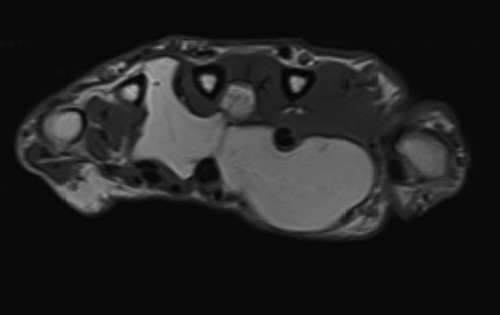

The patient underwent nerve conduction studies, which suggested a carpal tunnel lesion on the left. Magnetic resonance imaging (MRI) of the left hand confirmed the presence of a large, lobulated and well-defined fatty lesion in the palm centred between the flexor tendons and metacarpals, with dorsal and volar extensions (Fig. 1), and a proximal component within the carpal tunnel causing median nerve compression (Fig. 2). The investigations were discussed at the regional sarcoma multidisciplinary team meeting and findings were suggestive of a benign lipoma.

Coronal section demonstrating small proximal extension into carpal tunnel with resultant median nerve compression.